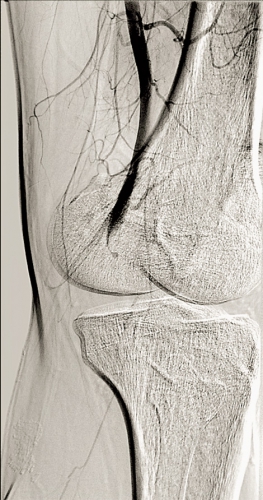

Cystisk degeneration i adventitian ger upphov till en gelatinös bildning i hålrum (Figur 2), som kan komprimera artären och ge symtom i form av artärinsufficiens [5, 6]. Det finns beskrivet i flera artärer men helt dominerande är a poplitea. Det första fallet beskrevs i Sverige 1954 av ortopeden Tor Hierton och internmedicinaren Börje Ejrup [7]. Innehållet i cystan påminner om innehållet i ganglier och har också vissa biokemiska likheter med ledvätska. Patogenetiska mekanismer som föreslagits är mikrotrauma, regelrätt ganglionbildning, myxomatös degeneration av adventitian eller kvarvarande synoviala celler med vätskeproduktion.

Typiskt symtom är claudicatio hos yngre eller medelålders individer. Den angiografiska bilden är typisk med en timglasformad stenos. Behandlingen är öppen enukleation av cystinnehållet (Figur 2). Vid sekundära förändringar av artären (trombos, fibros etc) kan en bypass eller interpositionsgraft behövas. Perkutan aspiration har försökts men med stor recidivrisk, varför man avråder från det.